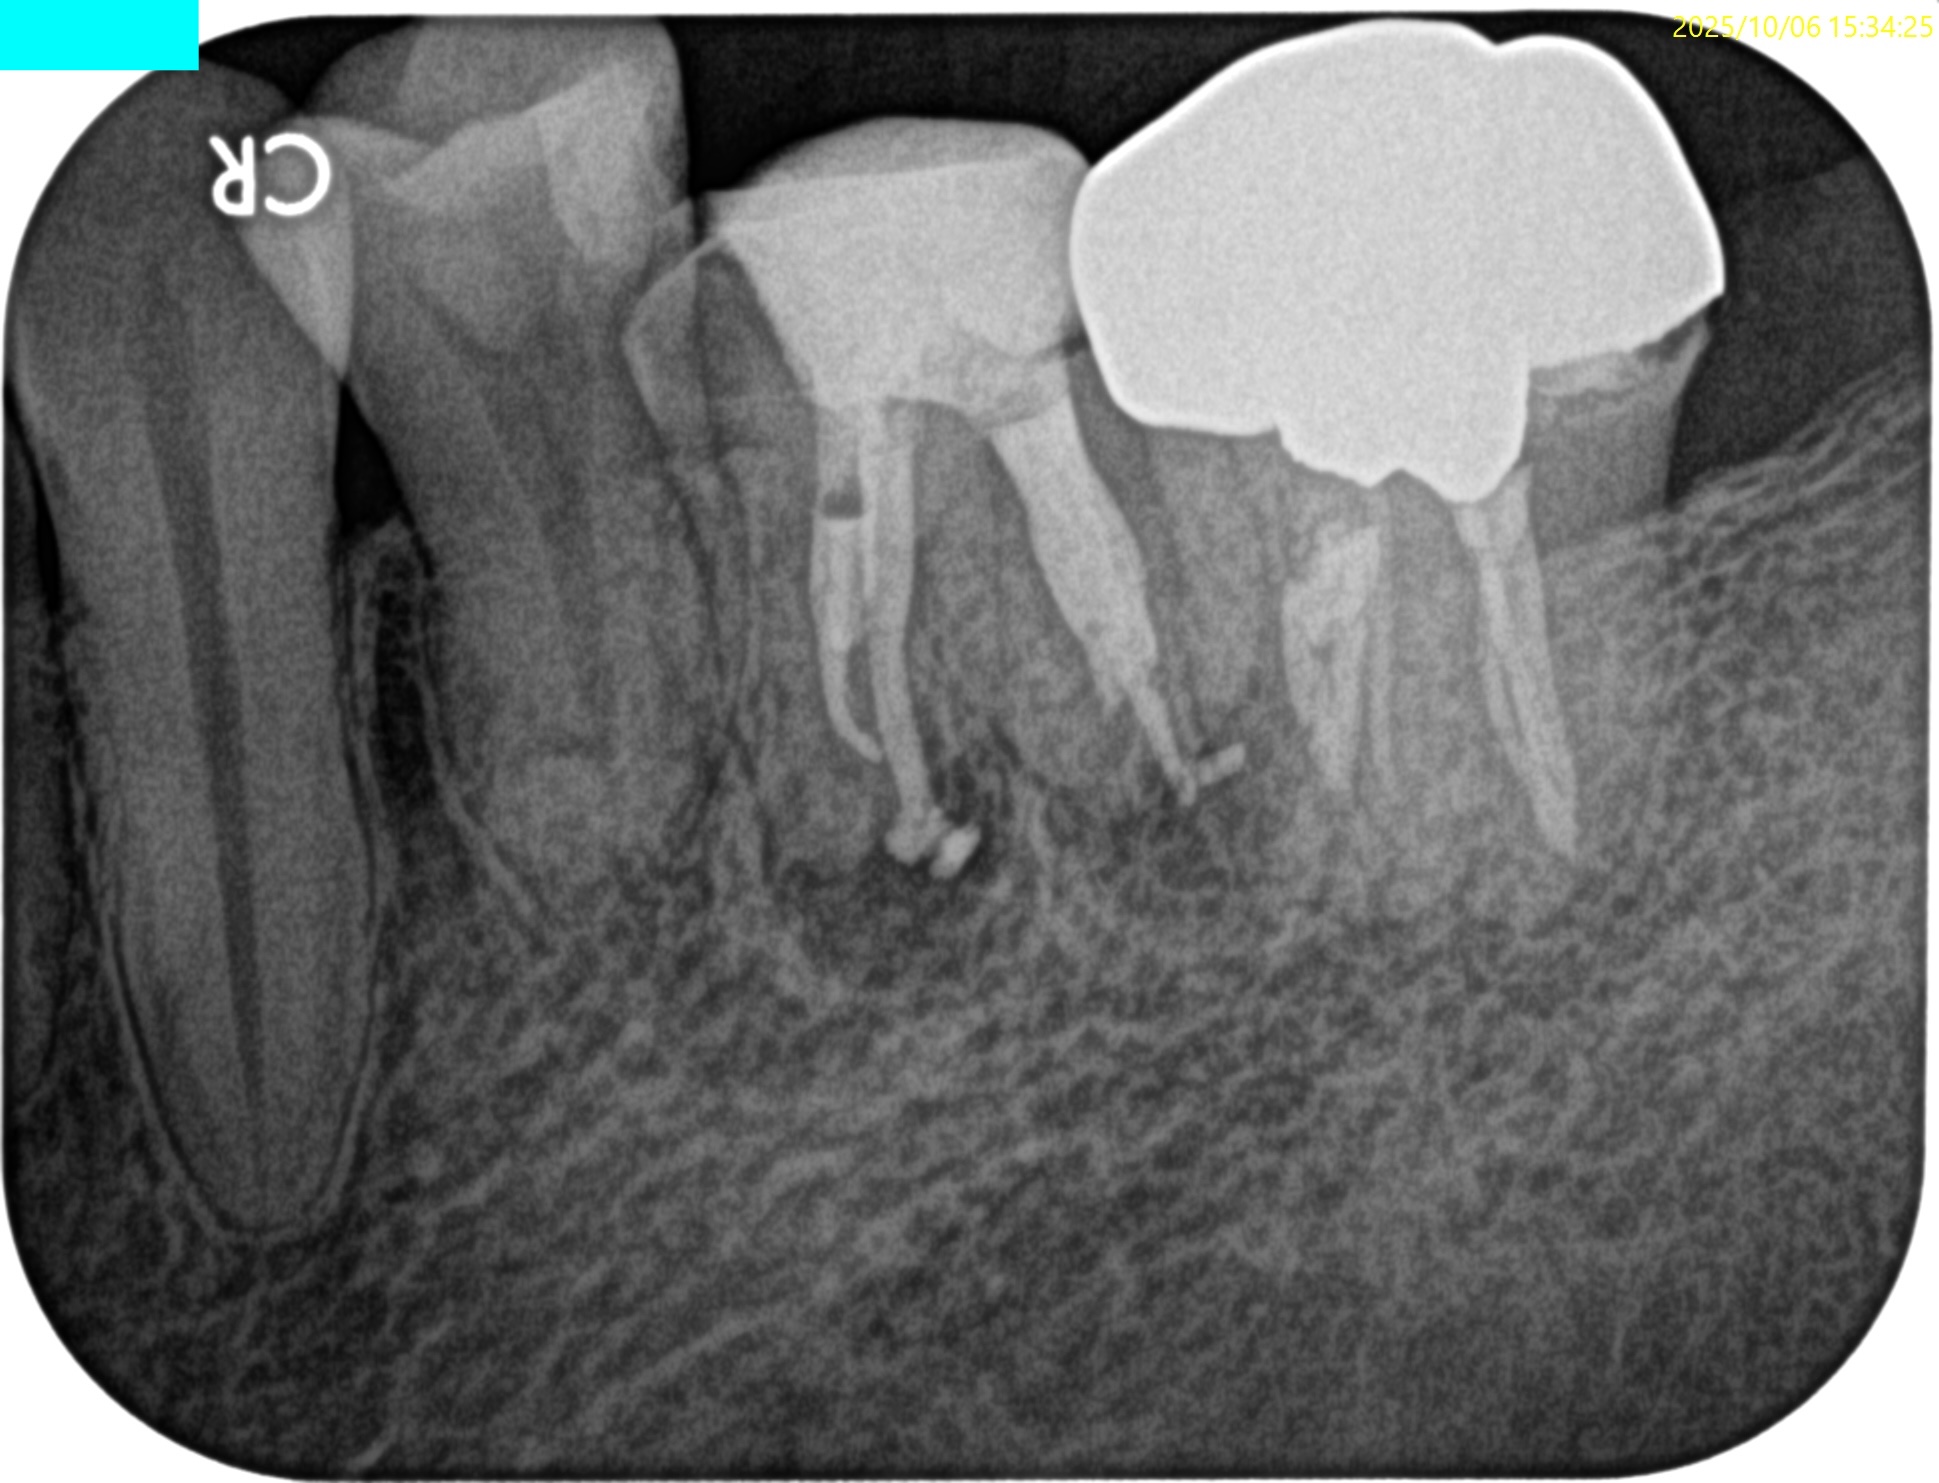

PA(2025.9.16)

MにもDにも病変がある。